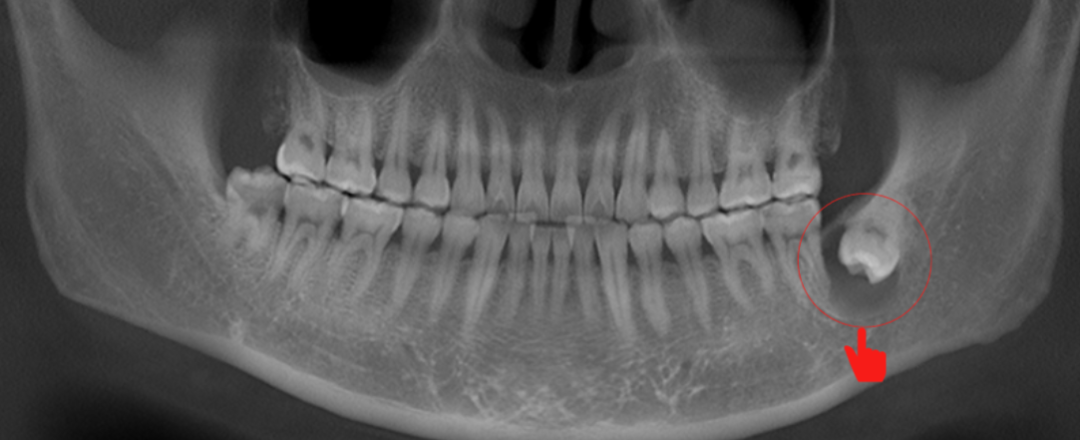

顶坏邻牙

牙齿松动

有些长歪了的智齿,还会把邻牙顶坏,导致邻牙牙根吸收、牙齿松动掉落。

如果是完全阻生的牙齿,还可能在骨内形成囊肿,造成下颌骨吸收,形态破坏。